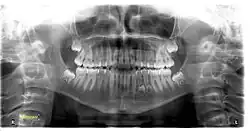

Tooth regeneration is a stem cell based regenerative medicine procedure in the field of tissue engineering and stem cell biology to replace damaged or lost teeth by regrowing them from autologous stem cells.[1]

As a source of the new bioengineered teeth, somatic stem cells are collected and reprogrammed to induced pluripotent stem cells which can be placed in the dental lamina directly or placed in a reabsorbable biopolymer[2] in the shape of the new tooth.[3]

In 2025, researchers at King's College London led by Ana Angelova Volponi reported the laboratory generation of early tooth-like structures using a hydrogel scaffold designed to support interactions between odontogenic cells. The engineered matrix was shown to encourage the organization of developing tooth tissue precursors, suggesting a possible way toward biological tooth replacement. Researchers noted that the constructs do not yet replicate the full morphology or function of natural teeth in humans, and the approach remains at an experimental preclinical stage. However, the development was described as a meaningful advance in regenerative dentistry and tooth repair research.[9][10][11] Researchers note that significant challenges remain before lab-grown teeth can be used clinically in humans. The lab work aims to improve interactions between cells involved in tooth formation, but methods for reliably replacing embryonic model cells with adult human cells have not yet been known. Possible future approaches if the research succeeded in humans, include partially growing a tooth in vitro before implantation into the tooth socket to complete development, or fully growing a tooth in the laboratory prior to surgical implantation. Researchers emphasize that these applications remain experimental and are not yet ready for clinical use.[12]

The majority of stem cell studies have stopped at the stage of animal studies and have not proceeded to clinical trials due to numerous safety and ethical concerns. The potential risks of undesired tissue formation, tumourigenesis, and metastasis have not yet been resolved.[13]